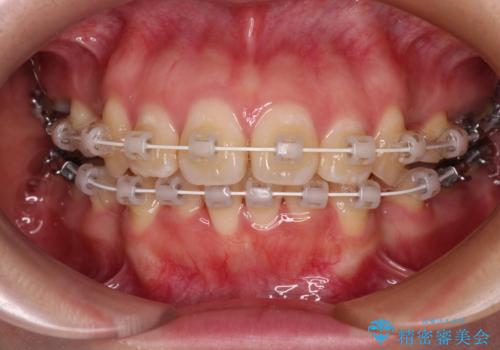

- 矯正装置

- 審美装置

突出感の強い上顎前歯をしっかりと後方移動させるため、上顎の裏側の補助装置(リンガルアーチ)とアンカースクリューを併用しています。

上下左右の第一小臼歯を抜歯して、目立ちにくいワイヤー装置で矯正を行いました。